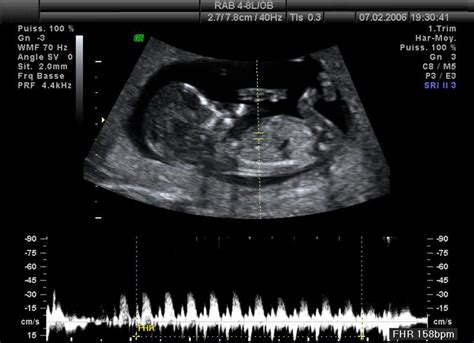

Pred pôrodom sa často vykonávajú častejšie kontroly, vrátane ultrazvukového vyšetrenia funkčnosti placenty. Dôležité signály naznačujúce blížiaci sa pôrod sú silnejúce kontrakcie, uvoľnenie hlienovej zátky (ktorá môže obsahovať prímesy krvi) a prípadne odtečenie plodovej vody. Tieto prejavy môžu byť sprevádzané aj hnačkou, pálením záhy, nevoľnosťou či únavou. Na rozdiel od cvičných kontrakcií (poslíčkov), predpôrodné kontrakcie sú silnejšie, bolestivejšie a pravidelnejšie, pričom sa ich frekvencia postupne zrýchľuje.

Diagnostika rastu plodu sa vykonáva počas tehotenstva pomocou ultrazvukovej biometrie. Včasné zachytenie tehotenskej cukrovky u matky je dôležité pre prevenciu nadmerného rastu plodu.